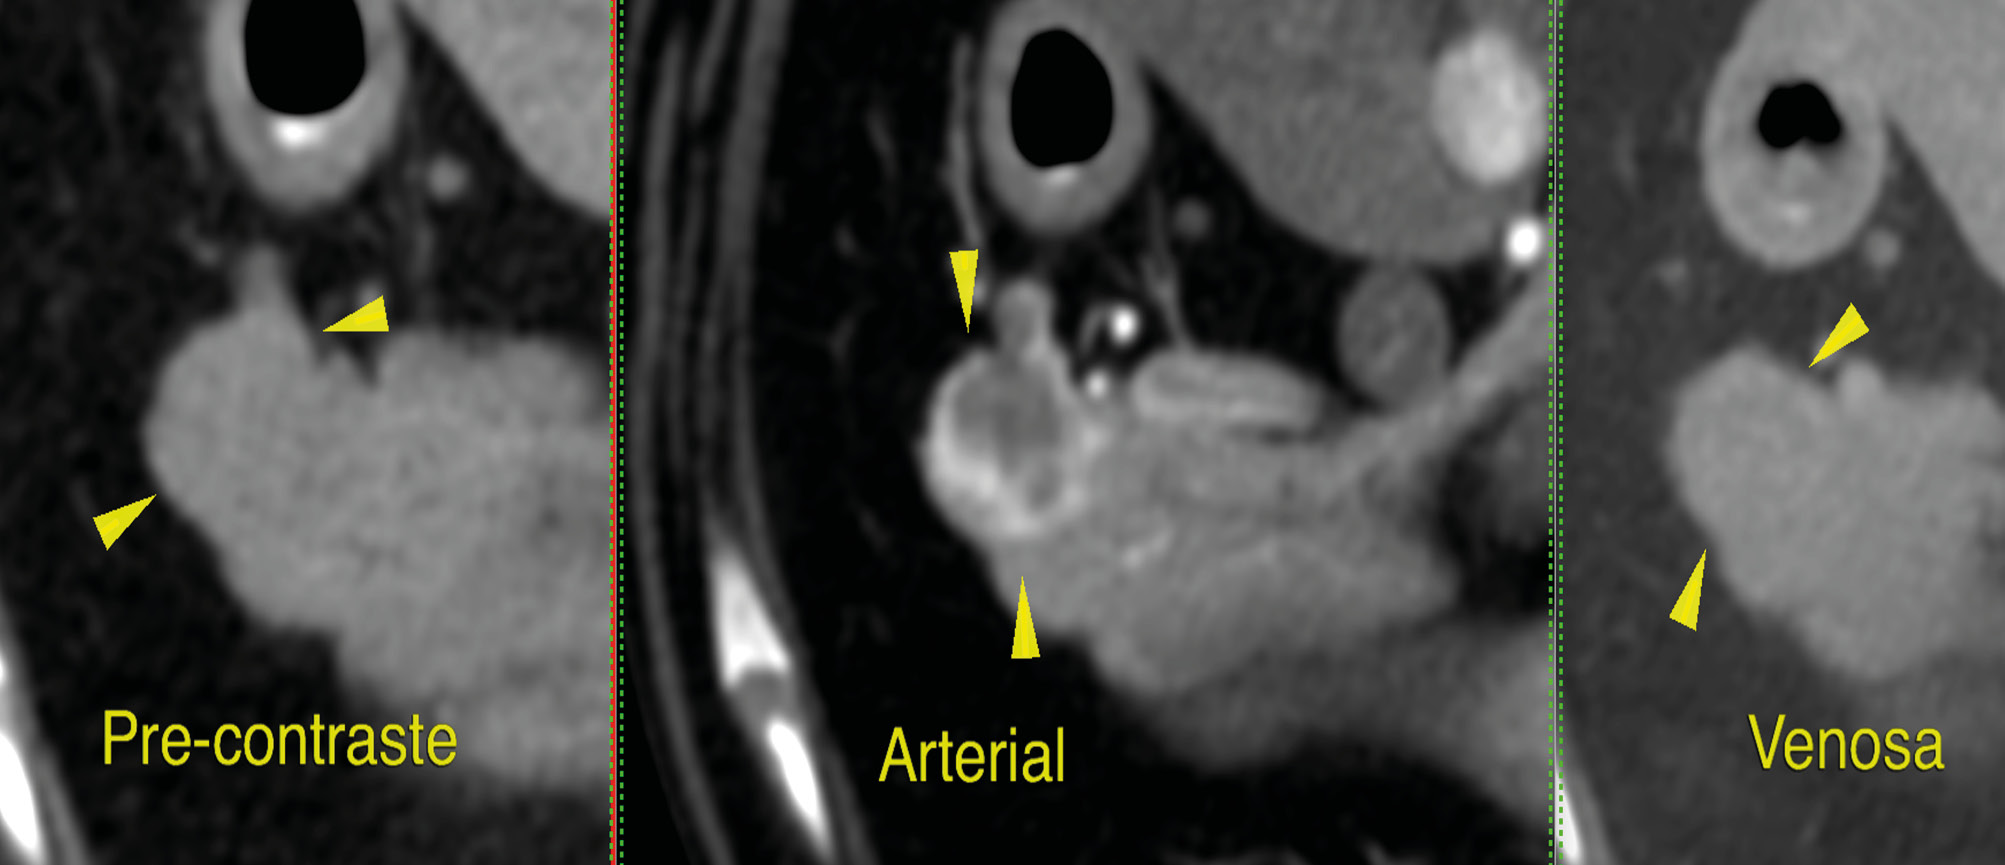

La tomografía computarizada (TC) puede ser particularmente útil en la investigación de insulinomas, puesto que el gas en el tracto gastrointestinal no supone una limitación y es una prueba más sensible en la identificación de pequeñas lesiones, aunque para ello se suele necesitar la TC de fase dual. El insulinoma se caracteriza por presentar una imagen de nódulo hipoatenuante con un gran refuerzo, únicamente en la fase arterial del estudio (halo de contraste alrededor del nódulo) y no en otras fases (imagen 1).